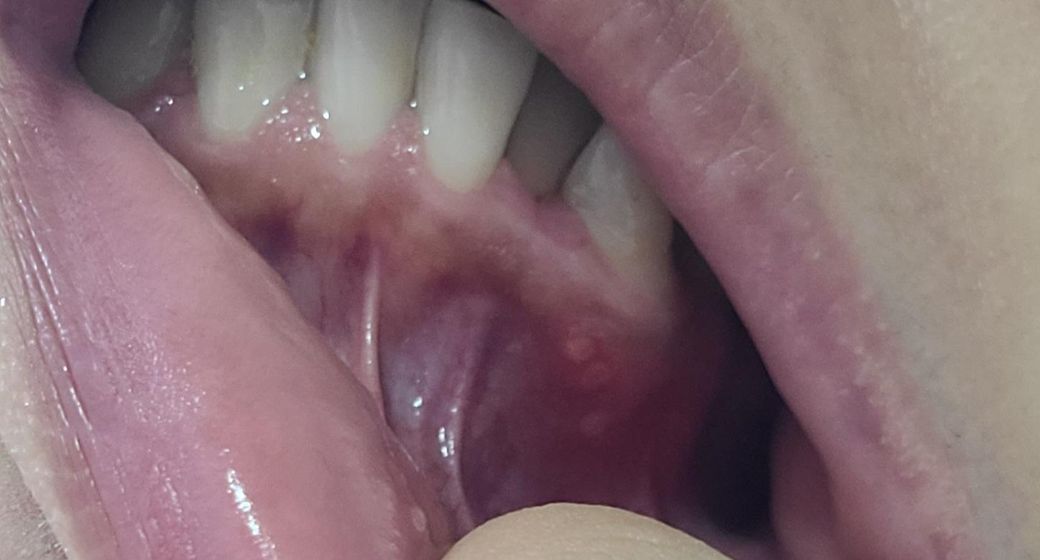

잇몸에 보이는 바와 같이 고름 염증 뾰루지같은게 낫는데요 잘때나 평상시 불편함없고 밥먹거나 물마실때도 불편함이 없지만 잇몸 뾰루지 부위에 혀로 누르거나 얼굴피부로 해당부위쪽을 누르면 통증이 있어요!

사진에 보이는건 단순 구내염같으니 치과에 가셔서 약을 바르시거나 그냥 지내셔도 크게 문제가 되진 않을것같습니다.

치조골에 염증이 있는 경우에 사진과 같이 뾰루지가 보일 수 있습니다. 염증이 생기는 원인은 치석이나 뿌리에 금이 같거나 신경관에 감염이 되었을 경우 등 여러 가지 원인이 있을 수 수 있습니다. 정확한 확인을 위해서 치과에서 진료를 받아보는 것을 권유드립니다

현재 치아 뿌리 부분에 염증이 생겨 고름이 찬것으로 보이며, 이 경우 치과에 방문하여 염증을 제거하는치료가 필요로 됩니다. 따라서 빠른시일내에 치과 진료를 받고 치료를 받길 권합니다.

만성 치주농양 같습니다. 염증의 기원이 잇몸인지 아니면 치아 속 신경쪽인지에 따라 잇몸치료를 할지 아니면 신경치료를 하게될지 결정될 것 같습니다.